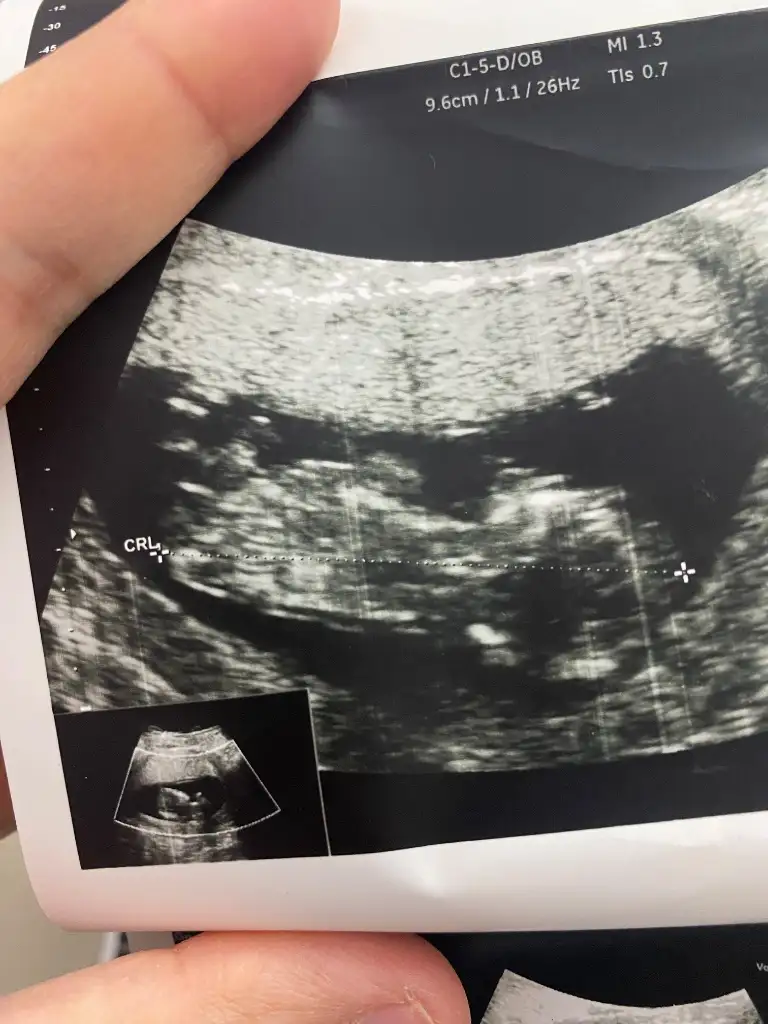

Valla canım bilmiyorum ki geçen hafta erkek dedi tam emin olamadım dedi bu hafta da göstermiyor dedi yaklaşık 20 dakika baktı da öyle kız dediAma çok erkek gibi duruyo yadoktor bi daha baksın

13 hafta cinsiyet nedir sizce yorumlar musunuz lütfenkız gibi

Kız gibi canım13 hafta cinsiyet nedir sizce yorumlar musunuz lütfen

13 haftalik bakarmiisniz karindanKızlar bebişlerinizin ultrason resimlerini ve cinsiyetini kaçıncı haftada olduklarını yazında kendi ultrason resimlerimizle kıyaslayıp fikirde bulunalım. Nub teorisi, kafa şekli, kemik yapısından cinsiyet teorileri tutuyor mu bakalım bir![]()